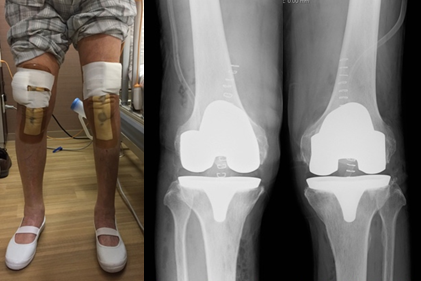

人工膝関節全置換術 (total knee arthroplasty: TKA)

- 末期の変形性膝関節症に対しては、TKAを行います。

患者さんの術前の膝関節可動域や画像所見を十分に検討し、それぞれに適したインプラントおよび術式を選択しています。また、手術精度の向上を目指したコンピュータナビゲーションを2機導入し、より正確な手術の達成や臨床研究のデータ解析に活用しています。 - さらにコンピュータ支援手術の開発を行なっています。

両側O脚変形、両側同時TKA